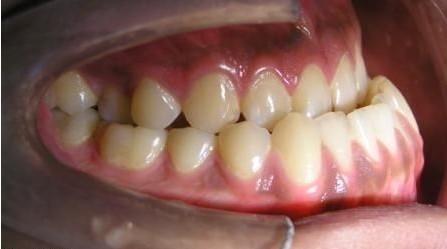

• 地包天,醫(yī)學(xué)上稱為“前牙反頜”,主要表現(xiàn)為下前牙咬在上前牙的外面。其成因較為復(fù)雜,可能是遺傳因素導(dǎo)致,也可能是不良的口腔習(xí)慣(如長期吮指、咬上唇等)、乳磨牙早失、乳尖牙磨耗不足等因素引起。

• 兒童地包天如果不及時矯正,會帶來諸多危害。首先,它會影響咀嚼功能,導(dǎo)致咀嚼效率低下,加重胃腸負(fù)擔(dān),進(jìn)而影響孩子的營養(yǎng)吸收和身體發(fā)育。其次,地包天會影響面部的正常發(fā)育,造成下頜過度前伸,上頜發(fā)育不足,形成“月牙臉”,影響面容美觀。此外,地包天還可能對孩子的心理健康產(chǎn)生負(fù)面影響,導(dǎo)致孩子自卑、孤僻等。